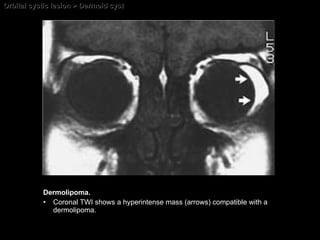

Orbital cystic lesion > Dermoid cyst Dermolipoma. Coronal TWI shows a hyperintense mass (arrows) compatible with a dermolipoma.